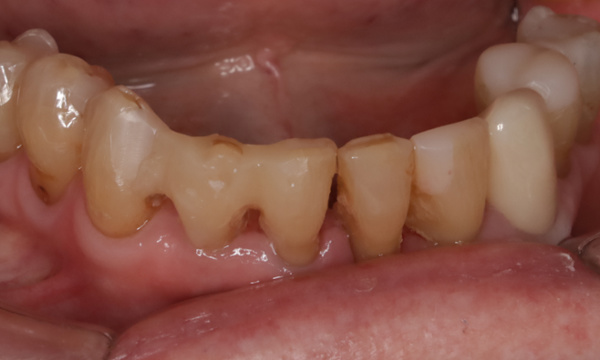

Zirconia Bridge from lower canine to canine

This patient had numerous fillings across the years on her incisors and canines. The incisors of the bottom teeth had become loose and infected, and she wanted replacement of them without implants.

We elected to provide a bridge which held on to her canines on either side, and remove (extract) the incisors and replace them with the bridge. We also placed zirconia crowns on her premolars.